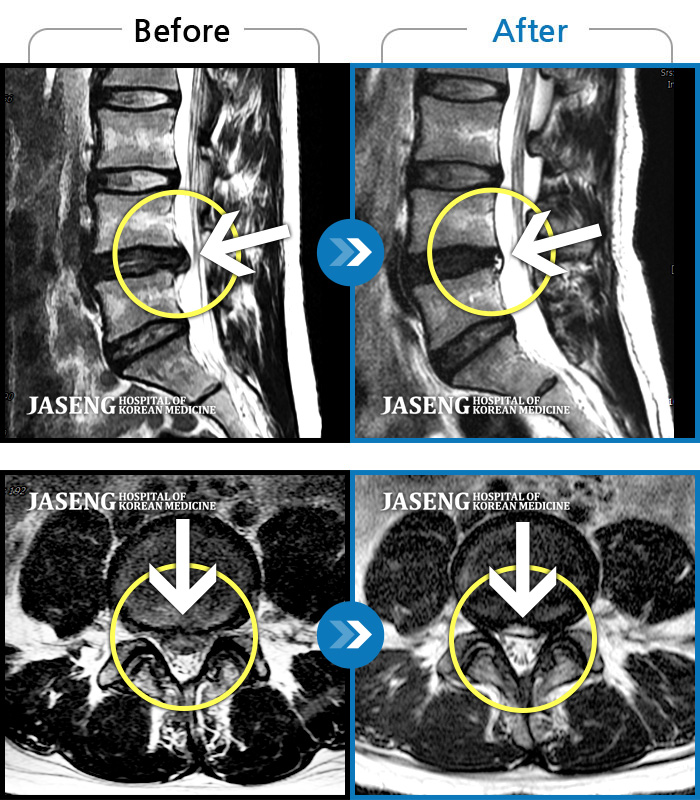

허리디스크

강남 · 강만호 원장

허리통증 및 왼쪽 다리 통증으로 운전이 불가능했습니다.

촬영시기

2023.10.16 ~ 2024.10.14

2024.10.23